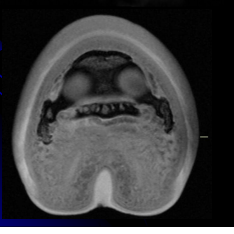

More adventures in Radiology recently. Pretty much everything in the horse's distal limb looks like an animal. We saw a badger with a chef's hat, a tiger sticking its tongue out, and a deformed cock and balls with a goat staring at them today in a skeletal lab. That was fun. But this is BY FAR the creepiest thing I've ever seen on a radiograph:

What that fuck?! It's so weird and distracting that I honestly have no idea what's actually going on in this radiograph. Why do horses have creepy gnomes in their hooves?! Its eyes are staring at me. I swear, there was something that looked like this on Ren and Stimpy at some point in time.